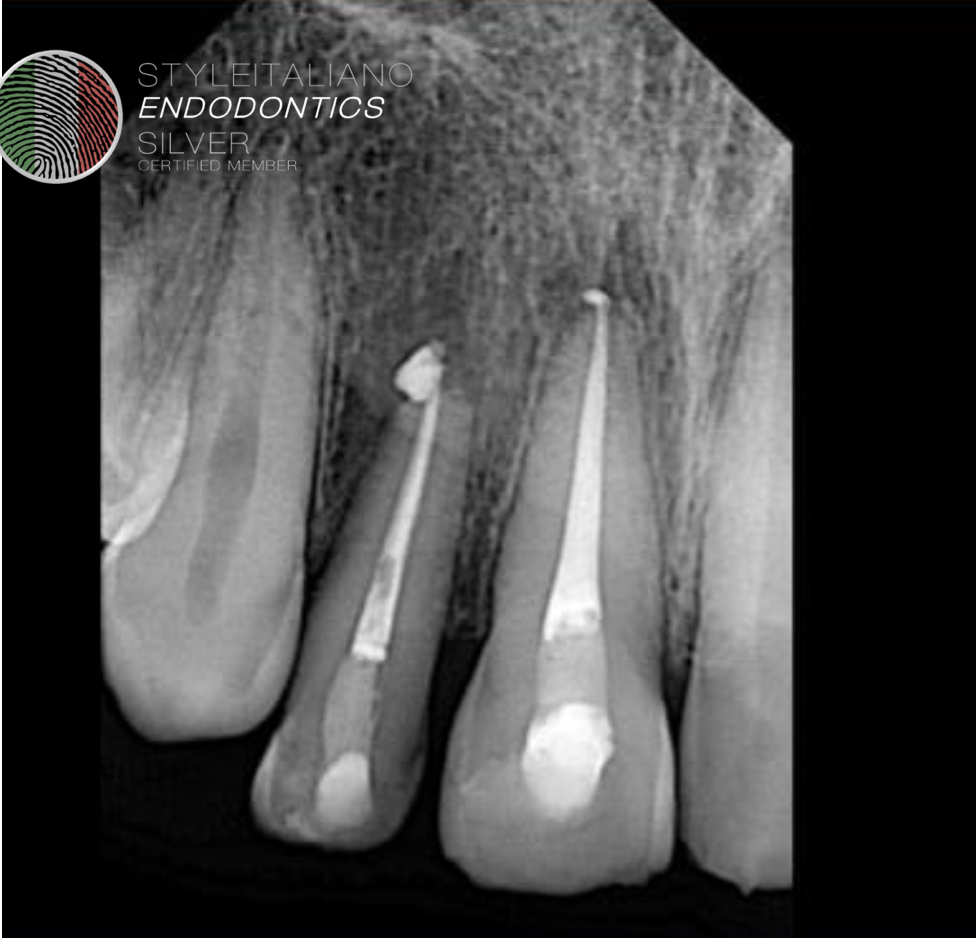

Fig. 5

Post operative radiograph.

Fig. 6

Follow up after one year.